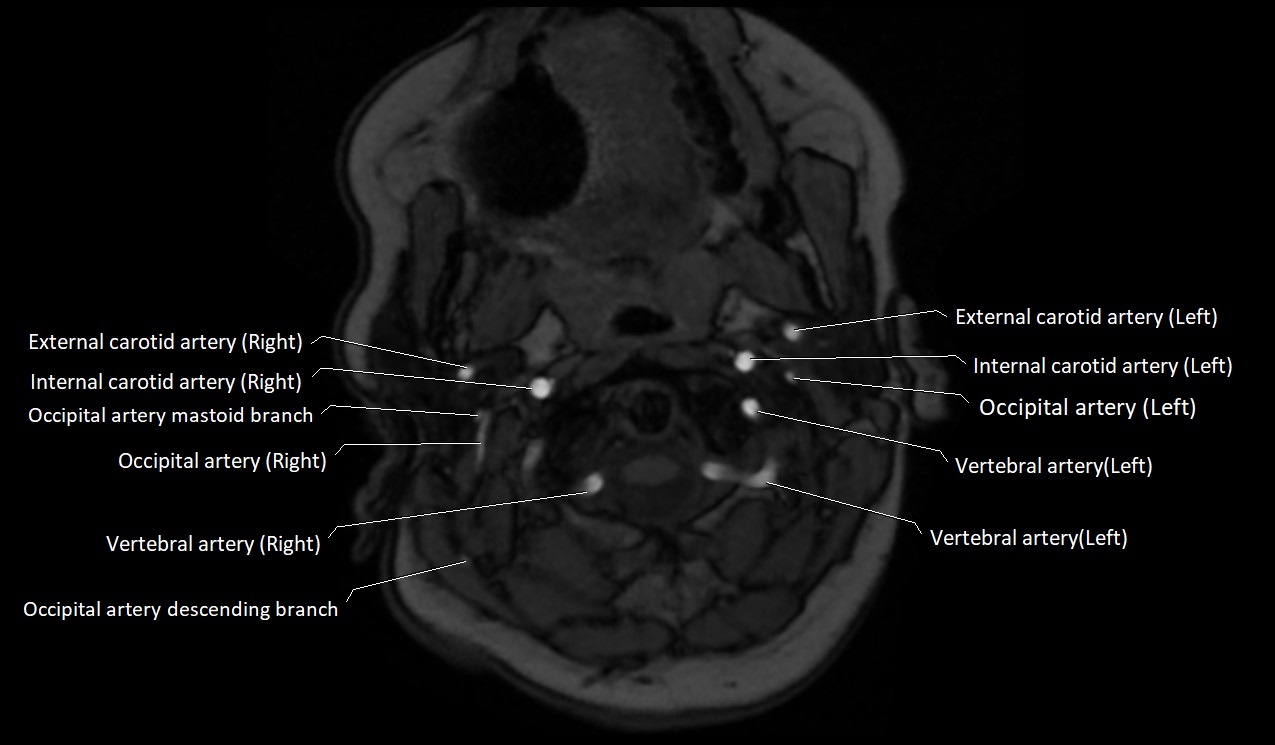

MRI Appearance:

• T1-Weighted Images:

• Appears as a tubular, hypointense (dark) structure relative to muscle

• May show flow void if the blood flow is fast

• T2-Weighted Images:

• Typically hypointense or isointense to muscle, but can be hyperintense if slow flow or stasis is present